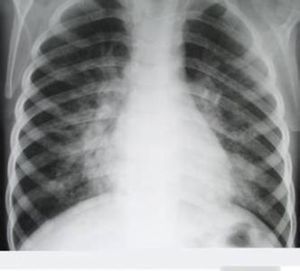

疾病早期,患者因毒血症而出現高熱、寒戰,外周血白細胞計數增高。因肺泡腔內有漿液性滲出物,故聽診可聞及濕性囉音,X線檢查肺紋理增粗。當肺組織發生實變時,臨床上則出現叩診呈濁音、觸覺語顫增強及支氣管呼吸音等典型實變體徵。由於肺泡腔充滿滲出物,使肺泡換氣功能下降,出現發紺等缺氧症狀及呼吸困難。以後滲出物中的紅細胞被巨噬細胞吞噬、破壞,形成含鐵血黃素混於痰中,使痰液呈鐵鏽色。隨著肺泡腔中紅細胞被大量纖維素和嗜中性粒細胞取代,痰液的鐵鏽色消失。並發纖維素性胸膜炎時可出現胸痛,聽診可聞及胸膜摩擦音。X線檢查可見段性或大葉性分布的均勻密度增高陰影。隨著病原菌被消滅,滲出物溶解、液化和清除,臨床症狀減輕,肺實變灶消失。X線表現為散在不均勻的片狀陰影。若不出現併發症,本病的自然病程為2周左右,若早期套用抗生素可縮短病程。

早期僅見肺紋理增粗或受累的肺段、肺葉稍模糊。隨著病情進展,肺泡內充滿炎性滲出物,表現為大片炎症浸潤陰影或實變影,在實變陰影中可見支氣管充氣征,肋膈角可有少量胸腔積液,在消散期,X線顯示炎性浸潤逐漸吸收,可有片狀區域吸收較快,呈現“假空洞”征,多數病例在起病3~4周后才完全消散。老年患者病灶消散較慢,容易出現吸收不完全而成為機化性肺炎。

10.胸部X線檢查顯示段或葉性均勻一致的大片狀密度增高陰影。